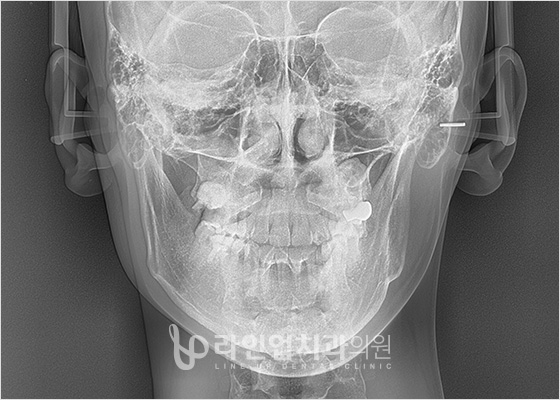

3D CT зураг авах

Өмнө ба дараах зураг

Before

After

3D Нарийвчлал оношлогооны систем

Энэ нь зөвхөн нүүрнтй яс төдийгүй үл үзэгдэх мэдрэл, цусны судасны байрлал, булчин, өөхний байдал, нүүрний яс, бүтэц, хөдөлгөөнийг төгс төгөлдөрт оношлодог.